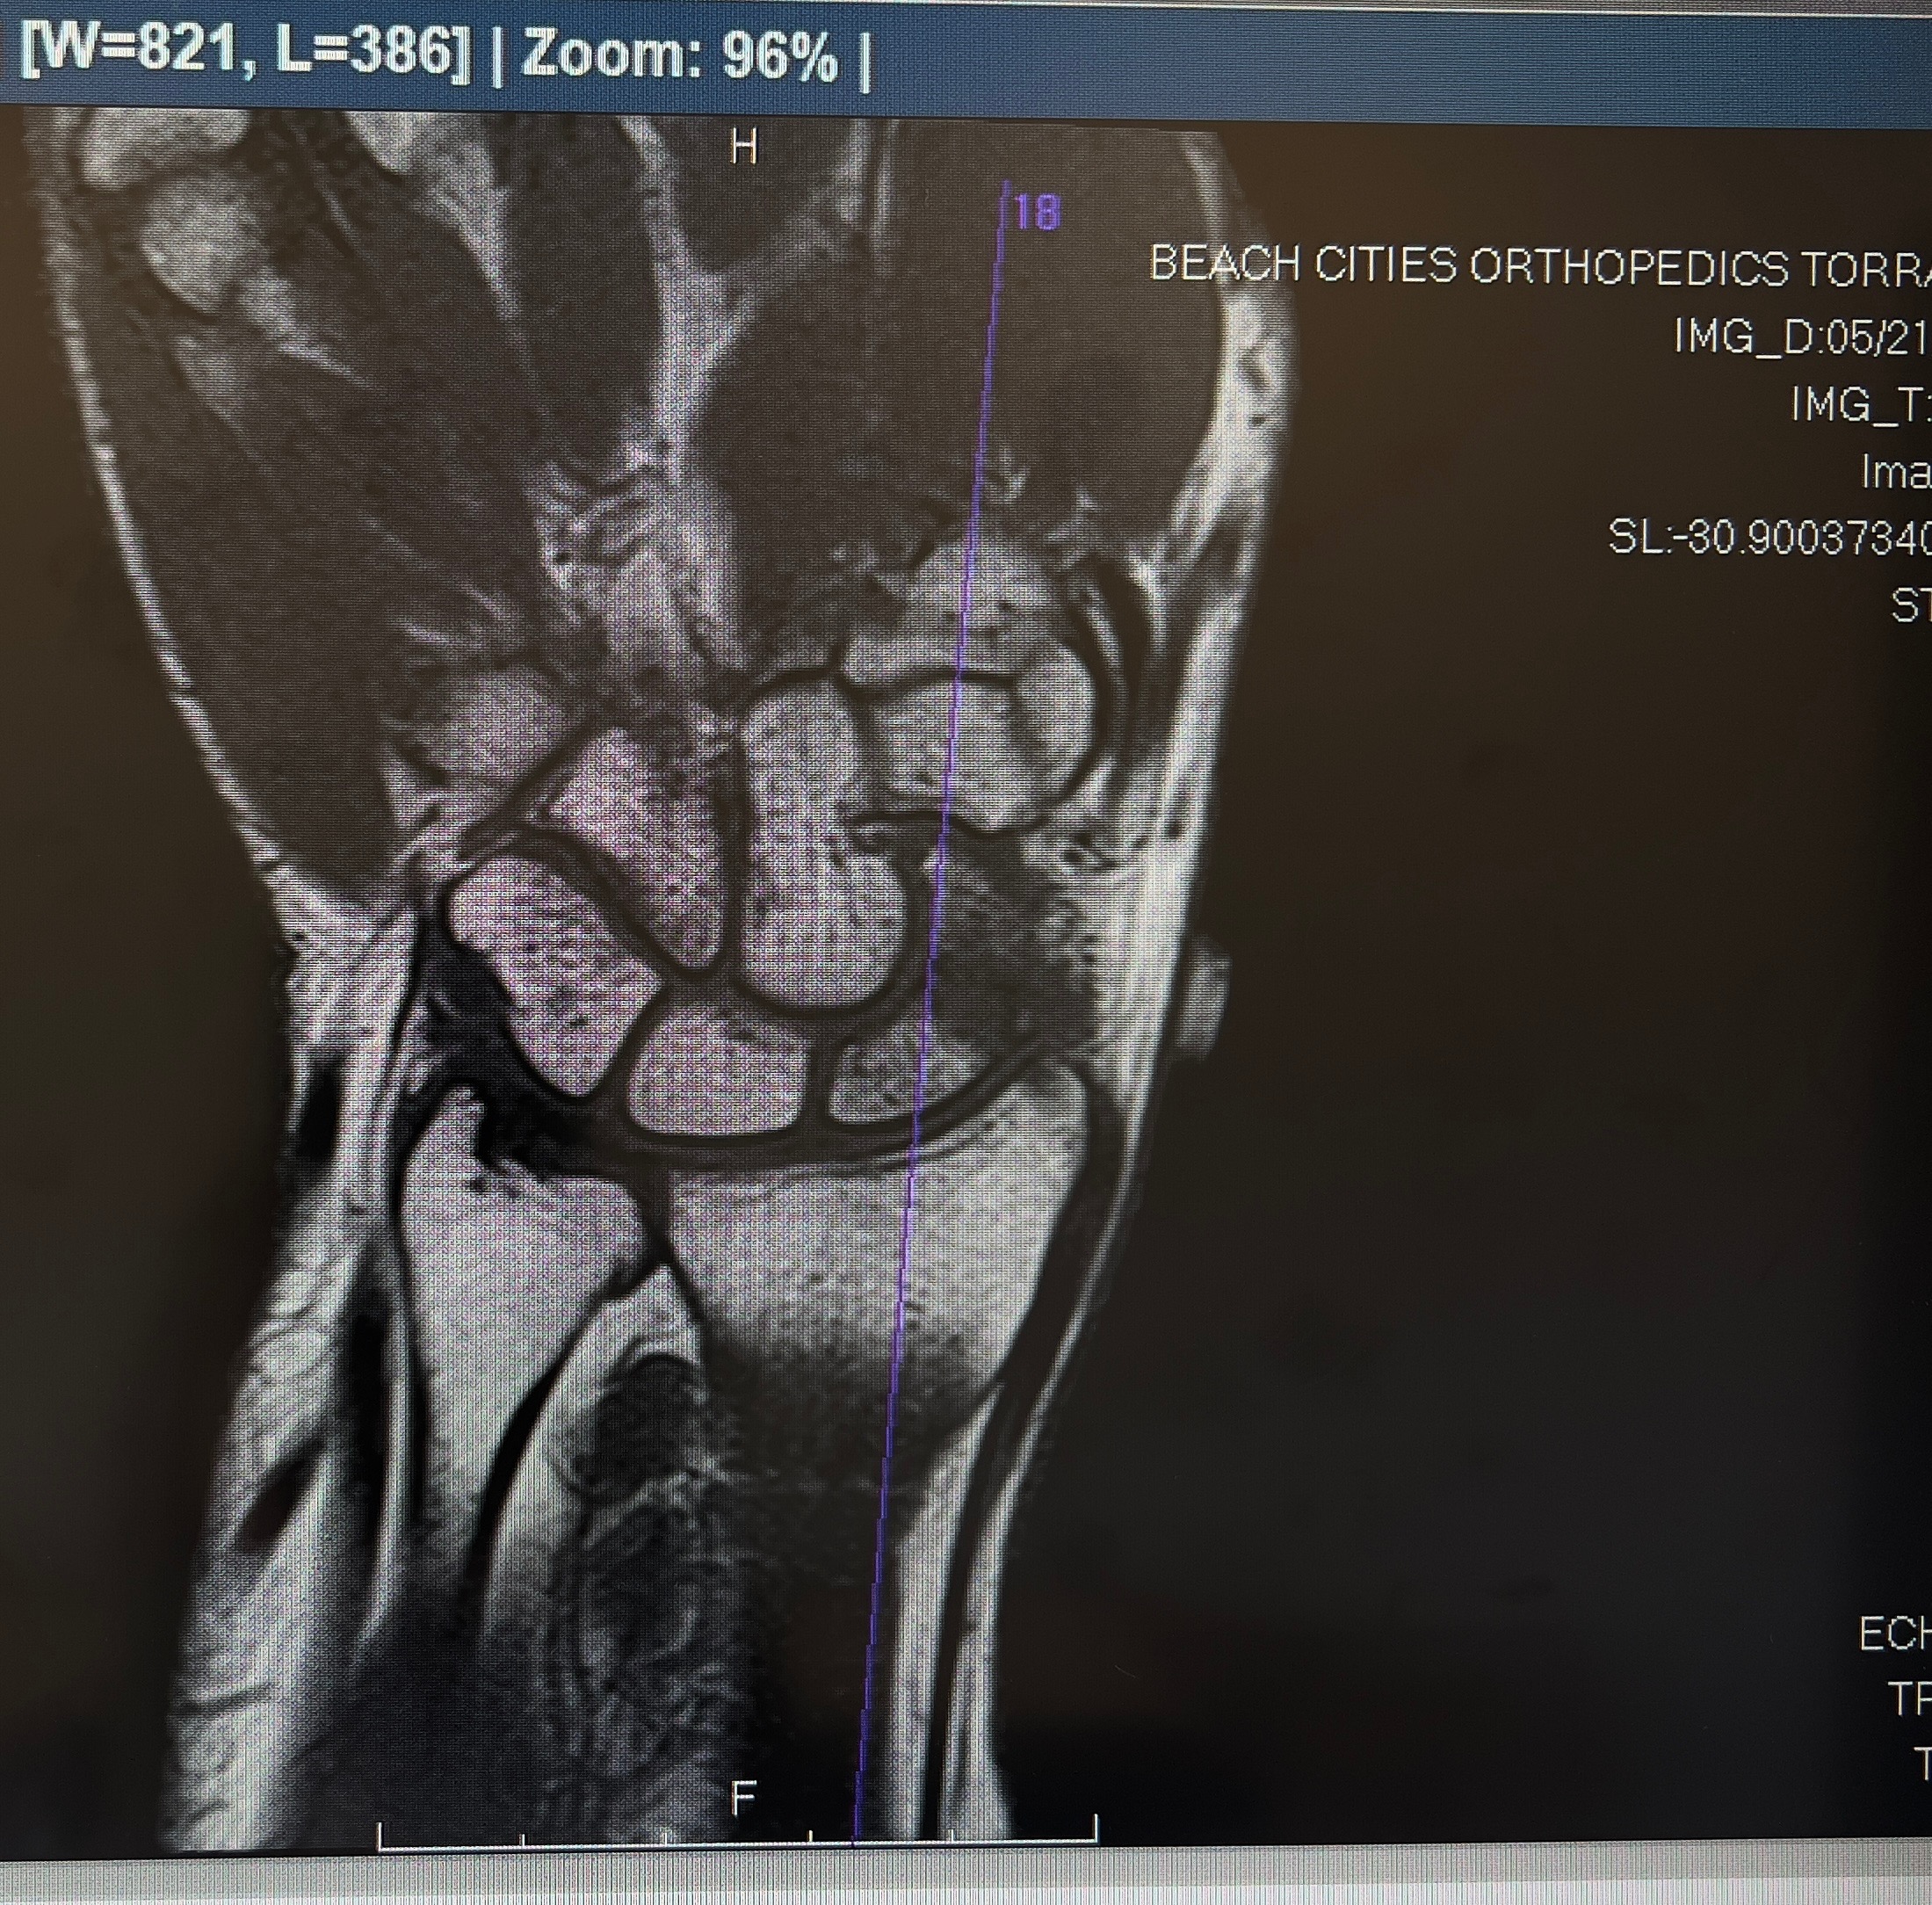

While shes since returned to work, it’s only been part-time as shes still recovering from a broken femur. Unfortunately, she now needs an additional surgery on her hand to insert a pin and undergo bone grafting. She will be in a hard cast for at least two weeks and unable to work during that time.